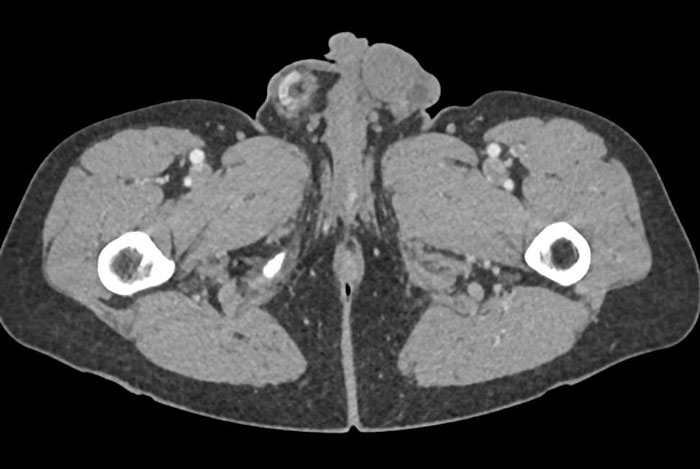

The case study says AI has great potential in the medical sphere

Image credits: Annals of Clinical Case Reports

According to the aforementioned case study, it is AI’s ability to learn and then imitate human reasoning, along with its integration into medicine, that made all these diagnoses possible.